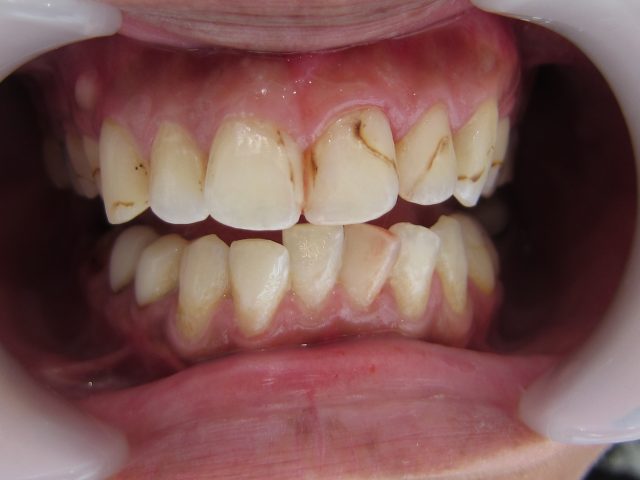

↓歯石を長い間、放置した為 こびり付いています。

そのため歯周病が進行し、周りの歯のほとんどが抜けてしまいました。

↓歯石除去後

歯石で覆われていた歯が顔を出しました